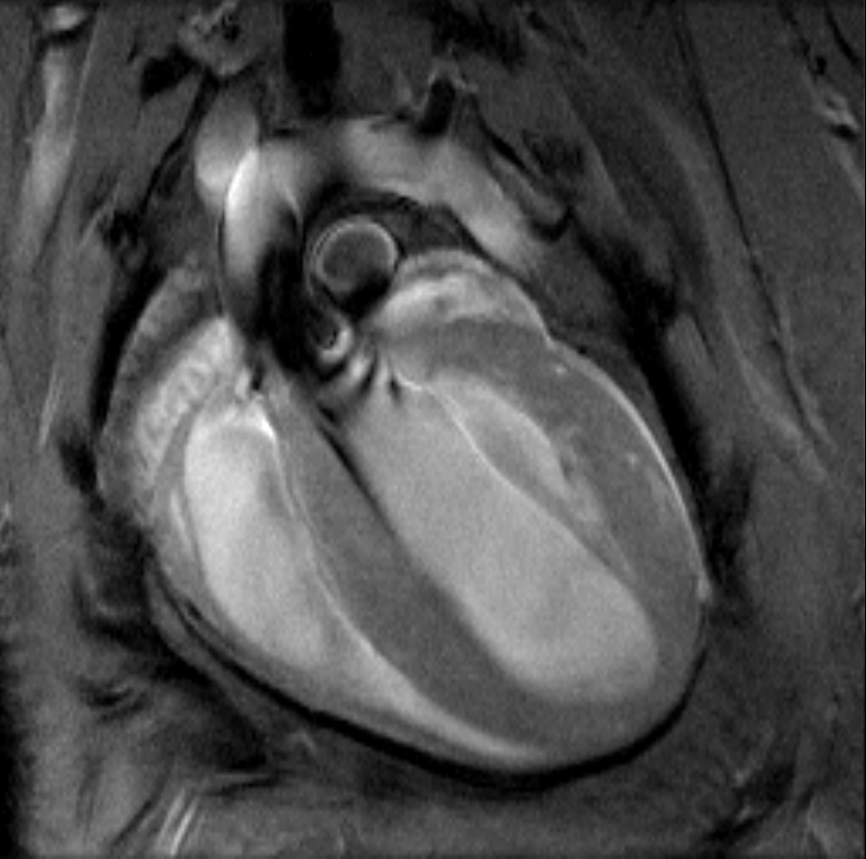

• Complete RF coil portfolio for mice and rats available, including coils for head, brain, cardiac, spine, body, multi-channel array coils with up to 8 channels, and x-nuclei

• MRI sequence portfolio of more than 1,000 sequence variations, including wireless cardiac imaging using navigator based IntraGate methods with cartesian or radial readout, as well as short echo time imaging, such as UTE and ZTE